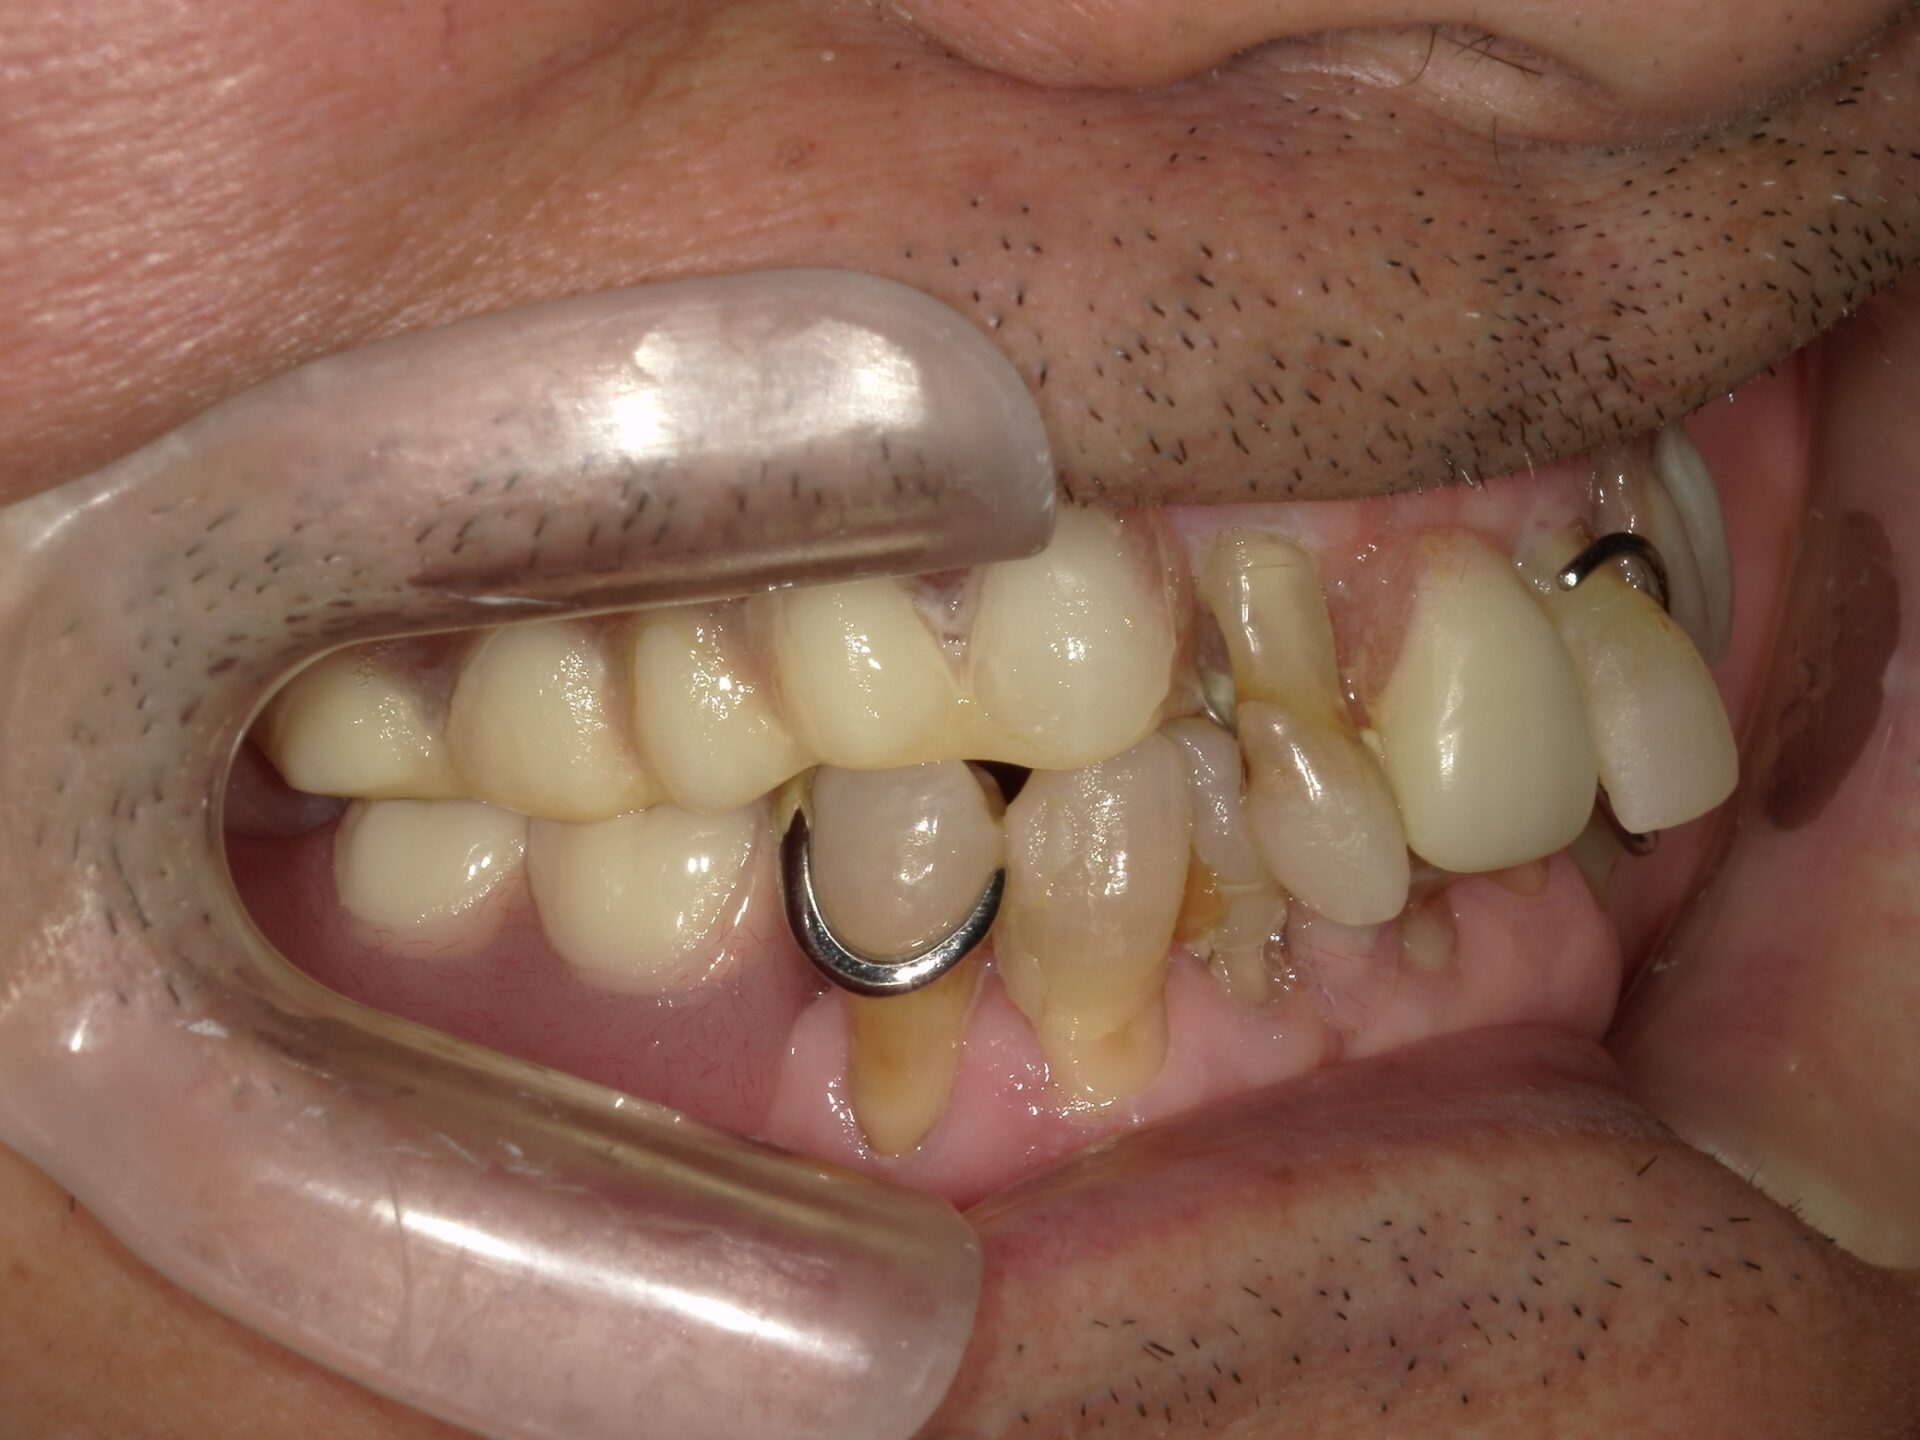

before

患者さんの年齢 50代 男性 症状 何も噛めない 治療内容 インプラント治療(オールオン4) 費用 費用900万(税抜) 治療期間・回数 治療期間2年・通院回数12回 メリット なんでも噛めるようになる 見た目が綺麗 デメリット・リスク 骨造成などで費用が増える場合がある - インプラント治療